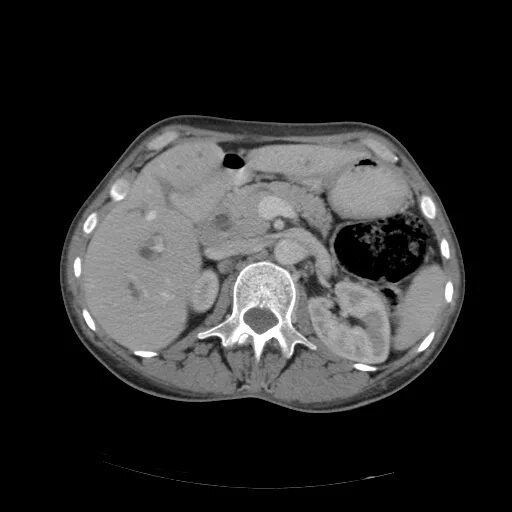

Кт брюшной полости краснодар